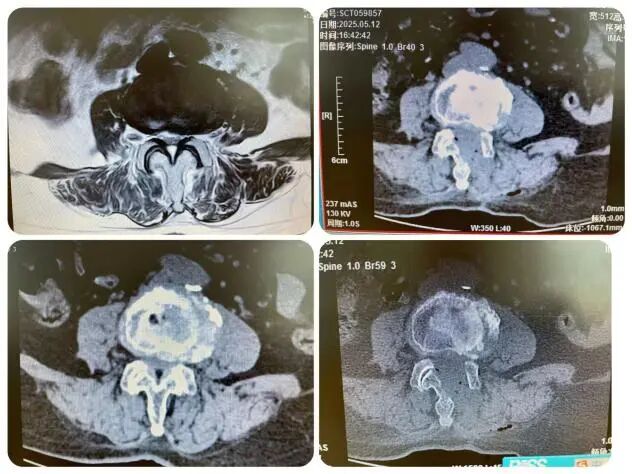

今年50岁的市民姚先生,腰腿疼痛已经一年多了,一直保守治疗,但效果不理想,总是反复发作,近期疼痛加重,稍走几步就感到下肢麻木剧痛,导致卧床不起,生活无法自理,苦不堪言。姚先生来到了邓州市人民医院骨外科三病区就诊。经过系统检查,姚先生腰5棘突叩击疼阳性,左下肢拖拽步态,踝关节背伸无力,小腿后方痛觉过敏,直腿抬高试验强阳性。 诊断为:1.腰5骨骶1椎间盘突出伴坐骨神经痛。核磁检查显示:腰椎退行性改变;L3—4、L4—5椎间盘膨出;L5S1椎间盘脱出(偏左);腰椎后方棘间筋膜炎。

“考虑到患者腰5/骶1椎间盘突出,髓核游离到狭窄的椎管内,开放手术因手术创伤大,视野欠佳,可能会有髓核的残留,导致术后症状不能完全缓解。”经过科室主任王志强和主治医生刘孟孟的综合评估、判定,决定采用更精准、高效且易操作的“单边双通道脊柱内镜下腰5/骶1髓核摘除术(UBE)”。